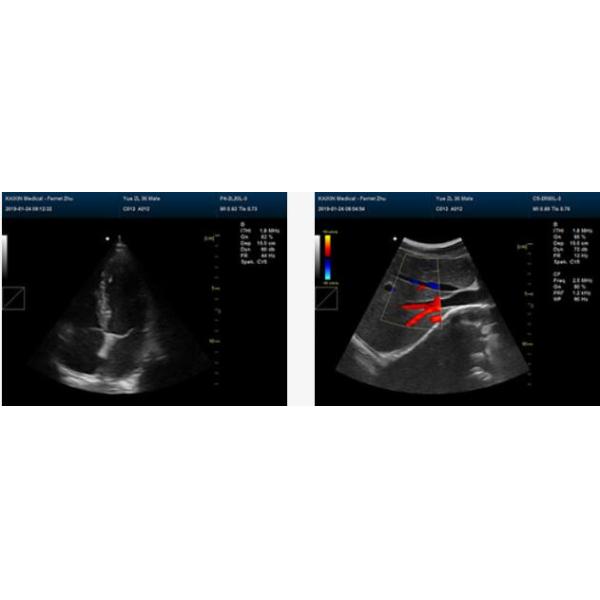

High Quality 2D Full Digital Color Doppler Machine For Pregnancy Test With Convex Probe

High Quality 2D Full Digital Color Doppler Machine For Pregnancy Test With Convex Probe Images |